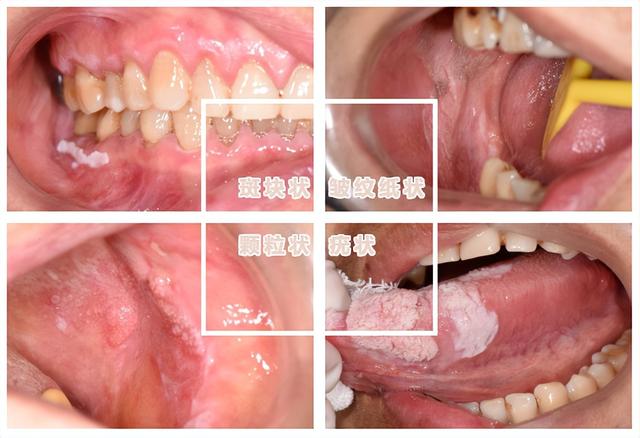

口腔白斑有多种形状:有一些带有绒毛状突起、摸上去硬硬的;有一些像皱巴巴的纸、摸上去很粗糙;有一些就是白色的斑块,中间可能有红色的糜烂,摸上去会有颗粒感......

颗粒状、疣状、糜烂溃疡型、念珠菌或HPV感染导致的口腔白斑,癌变风险会更大。(图很恶心,就不配图了)